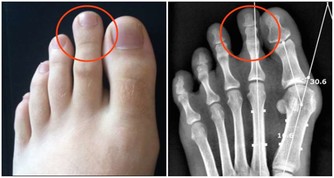

但有的人為了趕時間,排便時非常用力,這會使腹壓猛增,從而導致血壓升高,心跳加快,心肌耗氧量加大,嚴重時可誘發急性缺血,乃至心肌梗死。

與之相反的是,有些人“一入蹲坑深似海”,久久不願離開。但廁所蹲久了,會引發脫肛、痔瘡及直腸、子宮脫垂等疾病。